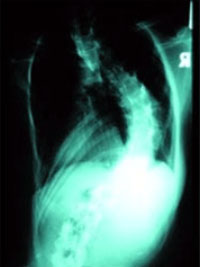

대개 진찰과 일반 엑스레이 사진 촬영으로 측만증의 종류와 골격 성숙의 정도를 알 수 있다. 가장 흔한 특발성 척추측만 증의 경우 엑스선 사진에서 측정한 각도가 20도 보다 작으면 3-4개월 마다 정기적인 관찰이 필요하며, 20도에서 40도 사이 는 대개 보조기를 착용시키는 치료가 필요하고, 40도 이상의 측만증에서는 수술적 치료를 신중히 고려하게 된다.

따라서 패드의 위치가 중요하며 보조기 착용 후 방사선 촬영을 하여 패드의 위치를 조정해야 한다.